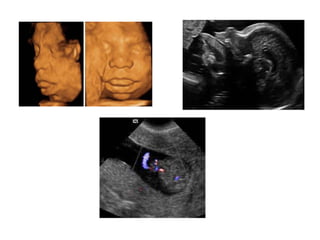

Binder Phenotype

a flat profile and depressed nasal bridge.

Short nose, short columella, flat naso-labial angle and

perialar flattening

Isolated Binder Phenotype transmission would be

autosomal dominant

Binder Phenotype can also be an important sign of

chondrodysplasia punctata (CDDP)

1. Chromosomal abnormalities: As Trisomy 21/4p del

2. Metabolic congenital abnormalities: As Zellweger syndrome.

3. Disruption of vitamin K metabolism: caused by inherited or

extrinsic factors

3.1 Inherited etiology: X-linked recessive brachytelephalangic

type of chondrodysplasia punctata = CDPX1 caused by mutations

of ARSE, localized in Xp22.3. ARSE codes Aryl Sulfatase Enzyme, a

system Golgi enzyme. His activity is inhibited in vitro by

Warfarin.

3.2 Extrinsic factors:

- Prenatal exposure to Phenytoin and Alcohol

- Prenatal exposure to Coumarin derivatives: especially between

6th and 9th weeks.

- Maternal chronic disease: with important vitamin K deficiency

during first trimester.